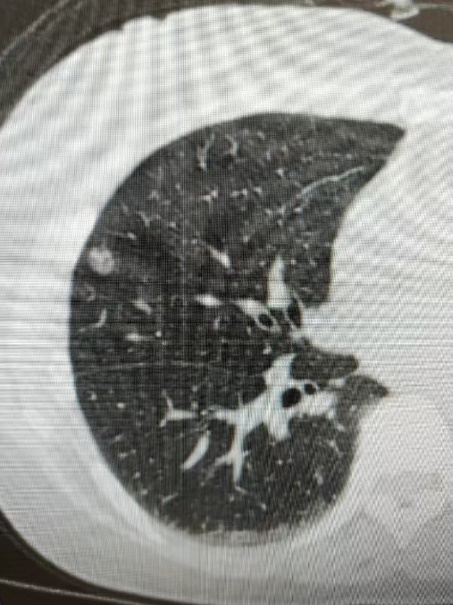

肺結節是指在肺部影像上出現的直徑≤3cm的圓形或不規則陰影,多數是良性,但也可能發展為肺癌。為幫助大家更好地了解肺結節,做到早發現、早診斷、早治療,我院組建了肺結節診療小組,開展肺結節專項診療,為廣大居民提供科學、便捷、貼心的肺結節早篩服務。

有一名女性患者,因咳嗽、咳痰40余天來院就診,行胸部CT提示:右肺上葉病灶,不排除肺癌可能。為進一步明確診斷,予以充分評估后,在CT引導下行經皮肺穿刺活檢術,病理結果顯示:(右肺)肺泡上皮異型增生,局灶結構紊亂,考慮腺癌,建議免疫組化六項檢查,為患者的后續精準治療提供了依據。